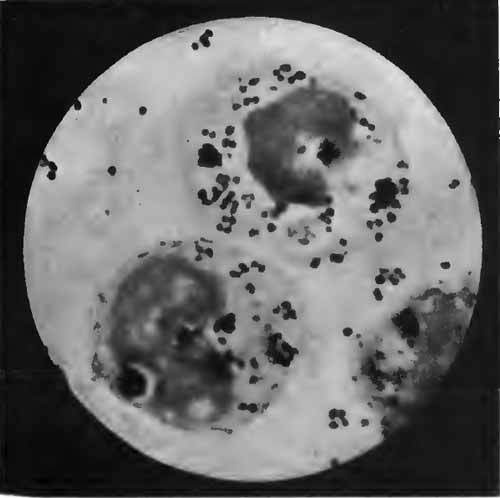

Diplococcus pneumoniæ in the blood

FIG. 9.—Diplococcus pneumoniæ in the blood (Fränkel and Pfeiffer).

Recognition of the pneumococcus depends upon its morphology, the fact that it is Gram-staining, and the presence of a capsule. Numerous methods for staining capsules have been devised, but few are satisfactory. Buerger's method is excellent. It is especially useful with cultures upon serum media, but is applicable also to the sputum. Smith's method usually gives good results, as does also the more simple method of Hiss (p. 263). The sputum should be fresh—not more than three or four hours' old.